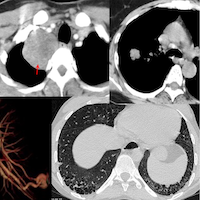

In patients with PH, radiologists can make a difference in identifying a few pathologies as causes of PH (leaving aside known cardiac and pulmonary diseases, where the conditions are already known). We should not miss these, especially shunts.

65-yrs old with PH and RV dysfunction for evaluation. Initially considered for edge-to-edge tricuspid repair.

CMR showed a cause of the PH, which could potentially change management.